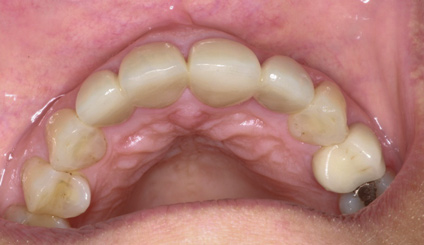

Reevaluation of this case 3 years posttreatment (Figure 6) revealed normal probing depths, no bleeding on probing, a significant improvement in the angular bone loss on tooth No. 7 (Figure 7), and a stable periodontal condition. Prosthodontic treatment was delivered in a healthy environment and provided a stable occlusion and a satisfying overall appearance (Figure 8 through Figure 10). Preservation of this esthetic outcome was a motivating factor for the patient to maintain a high standard of oral care. For financial reasons and in consideration of her low smile line, the canines were not involved in the prosthodontic therapy.

(6.) A 3-year, posttreatment photograph showing healthy tissue supporting the maxillary anterior teeth and correction of crowding.

Figure 6